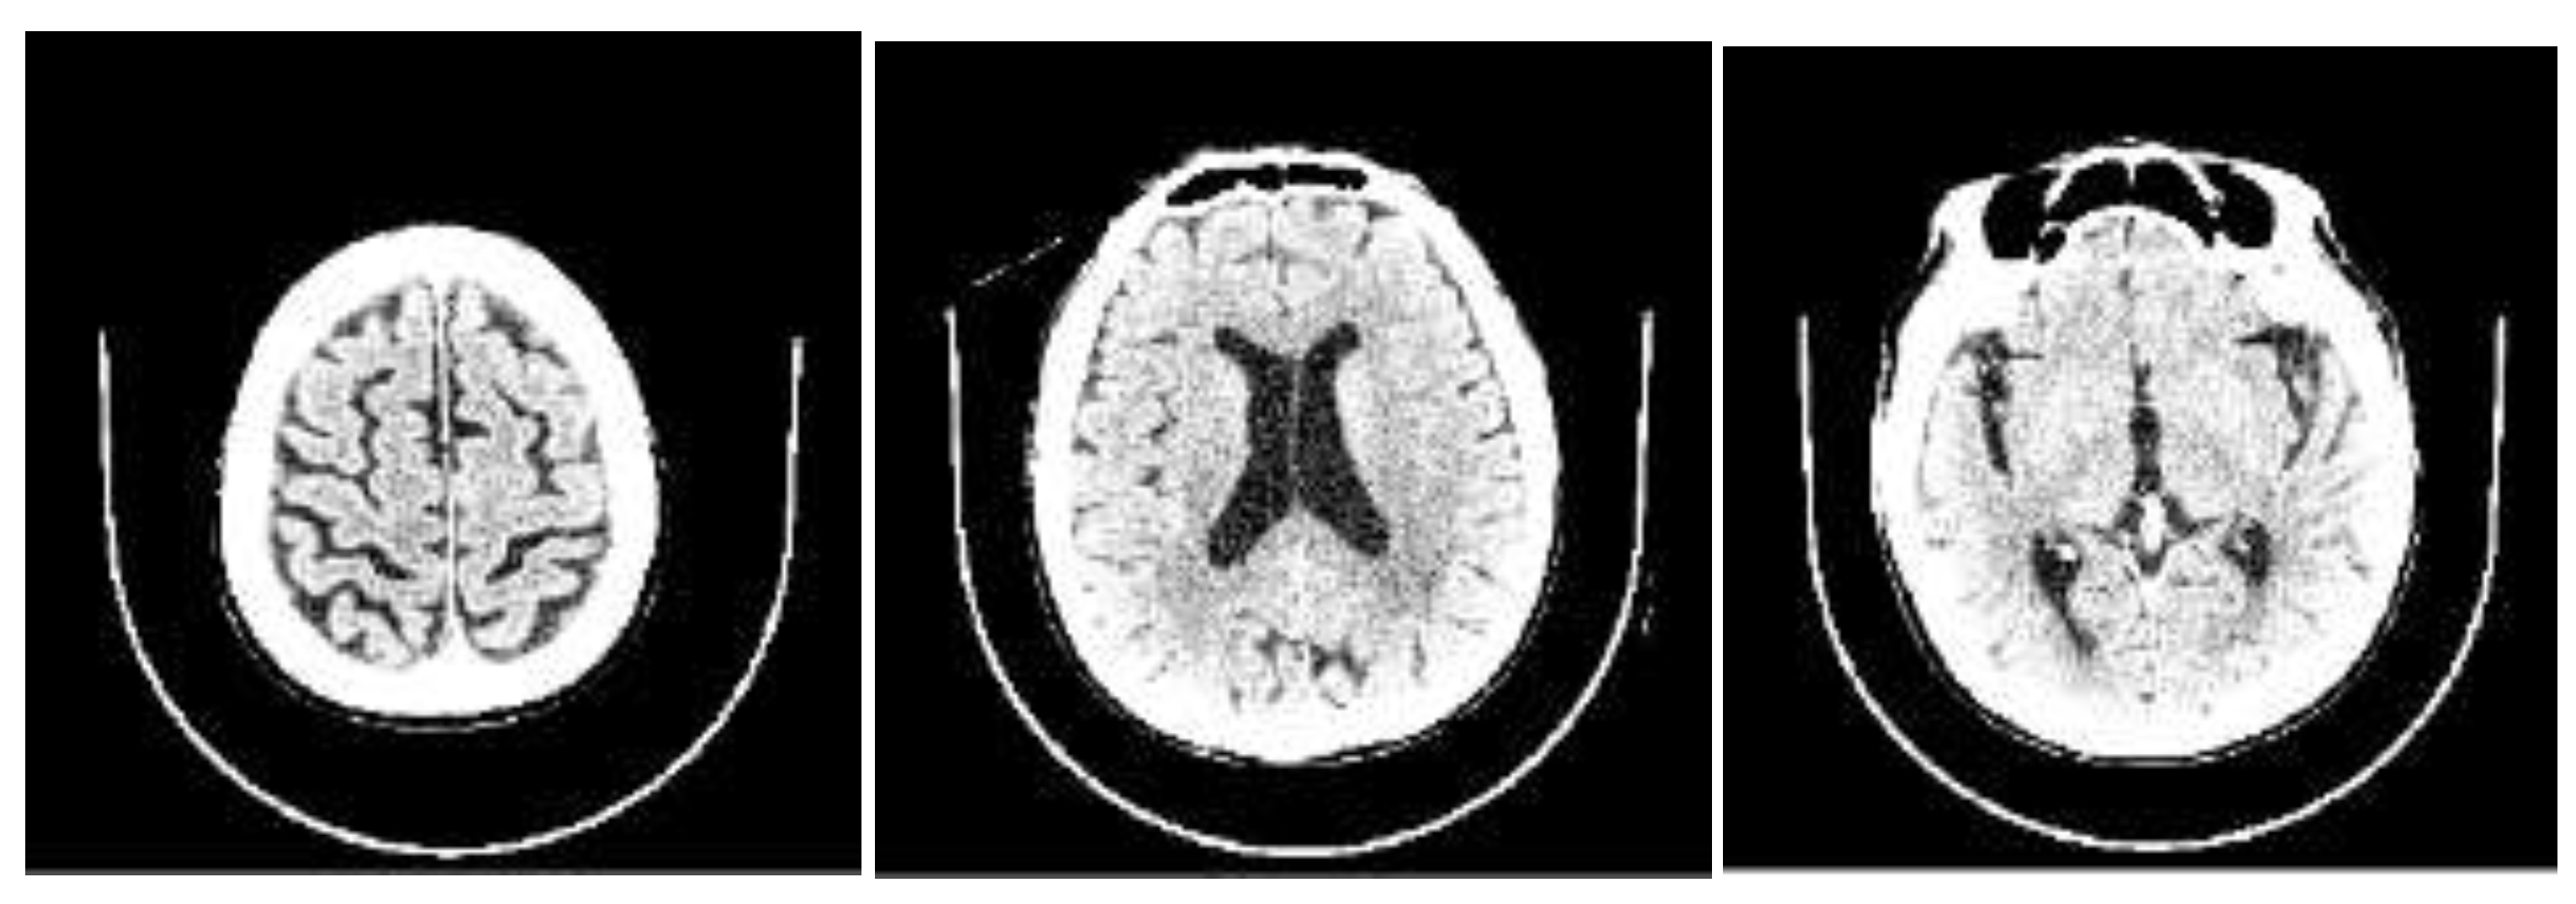

To gain insights into the factors influencing our AI model's predictions, we leveraged the SHAP library [https://github.com/slundberg/shap] to assess the impact of each feature when predicting the NPH probability for each CT scan. Our analysis revealed that the three most influential features were CSF ratio_8, CSF ratio_5, and CSF ratio_4 (refer to Figure 2). CSF ratio_8 captures changes in focal sulcal enlargement, while CSF ratio_5 and CSF ratio_4 correspond to enlarged ventricular regions (see Figure 3). This finding indicates that our AI model focuses on the key areas commonly examined by neuroradiologists during NPH diagnosis, underscoring its alignment with expert practices.

Figure 3. Samples of brain slice images from partition 8, 5, and 4, arranged from left to right that visually demonstrate the specific brain regions associated with the CSF ratios that play a crucial role in NPH prediction.